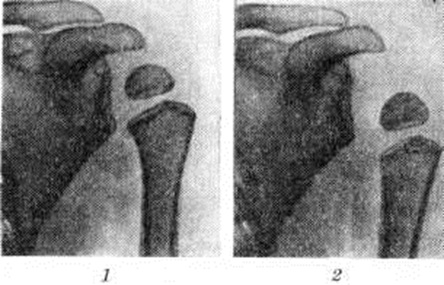

В связи с разболтанностью сустава и поворотом руки внутрь происходит проекционное смещение ядра окостенения головки плеча (рисунок 2), которое иногда приводит к ошибочному заключению о развитии при Дюшенна – Эрба паралич эпифизеолиза. В дальнейшем отчётливо выявляется остеопороз (смотри полный свод знаний) и атрофия костей плечевого пояса, особенно головки плеча и суставного отростка лопатки. Сравнительное изучение рентгенограмм плечевых суставов ребёнка показывает, что кости больной конечности уменьшены в размерах, порозны и атрофичны.

Рис. 2. | ||